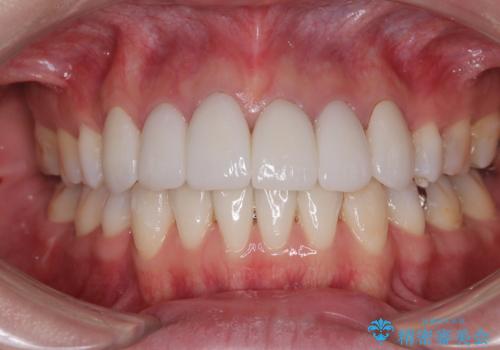

前歯が磨きにくい 目立たないワイヤー装置による矯正治療

歯列はきれいに整いますが、歯肉ラインは治療前の歯肉の位置を踏襲します。

特に八重歯であった歯は歯冠が長く見えますので、改善を希望される場合には、歯肉移植術を行う必要があります。